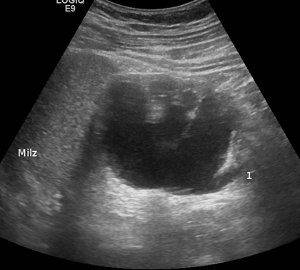

Для оценки состояния органов мочевыделительной системы используется экскреторная внутривенная урография. Данный метод представляет собой рентгенологическое исследование с использованием контрастного вещества. При проведении обычной визуализации мочевые пути просматриваются недостаточно хорошо. Обзорная внутривенная урография позволяет получать более полное представление о состоянии системы и отельных ее компонентов. Контрастное вещество проникает в кровоток. Из него оно попадает в почки и концентрируется в них. Далее контраст выходит по уретре вместе с мочой. За счет присутствия вещества происходит блокирование рентгеновских лучей в соответствии с почечной структурой. На снимках это имеет вид белых пятен. Изображения, полученные в ходе диагностики, называют внутривенными урограммами или пиелограммами.

Суть внутривенной урографии

При внутривенной урографии перед выполнением рентгеновских снимков в вену больного вводят раствор йодсодержащего контраста, который хорошо экскретируется почками и выводится через органы мочевыделения. Благодаря его скоплению в этих органах, наблюдающемуся уже через несколько минут после введения, врач может получать информативные снимки.

Обычно при внутривенной урографии первый рентгеновский снимок выполняется через 5 минут после введения контраста, второй – спустя 15 минут после выполнения инъекции, а третий – через 20 минут. Если на третьей урограмме определяется задержка контрастного препарата, то на 40-й минуте исследования врач выполняет еще один снимок.

Полученные при урографии снимки позволяют получить следующие данные:

- форма и контуры органов;

- аномалии развития;

- структура почечных лоханок, мочеточников, мочевого пузыря и уретры;

- мочевыделительная функция.